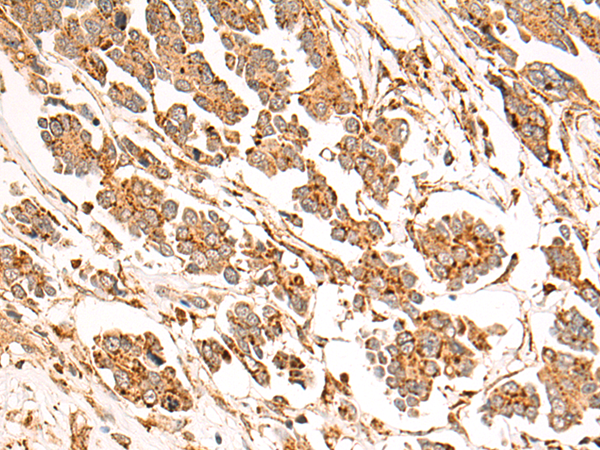

IHC positive control: |

Human colorectal cancer and Human liver cancer |

IHC Recommend dilution: |

50-200 |